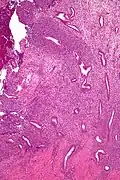

Low mag. Low mag.